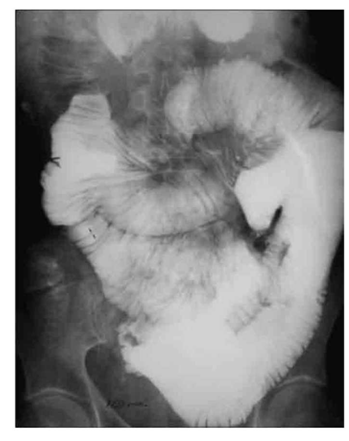

לעתים רחוקות, כדי לקבוע את גובה החסימה ואת מידתה בחולים הלוקים בחסימה דינמית, או כדי להבדיל בין שתי צורות החסימה, יש לצלם את החולה לאחר בליעת חומר ניגוד נספג מסוג גסטרוגרפין. בחסימה דינמית ניתן למצוא התקדמות של חומר הניגוד עד לחסימה (תצלום 6.4), ואילו בחסימה אדינמית ניתן למצוא אמנם מעבר לכל אורך המעי, אך מעבר איטי ביותר. לחולים שבהם יש חשד לחסימת הכרכשת, אין לתת בריום דרך הפה אלא לבצע חוקן בריום תחילה. ב- CT בטן עם חומר ניגוד ניתן לראות לולאות מורחבות שלאחריהן לולאות התמט, בצקת של הלולאות ונוזל ביניהם (תצלום 7.4).